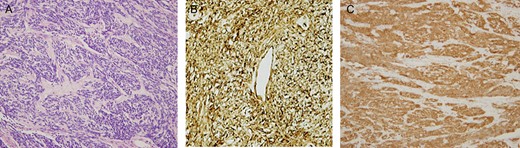

A 68-year-old male presented to our hospital after experiencing exertional dyspnea and shortness of breath for 2 months. He had no other chest complaints, such as cough, hemoptysis or chest pain. His medical history was unremarkable and he had no history of exposure to asbestos. He had no exposure to tobacco. His blood pressure was 136/78 mmHg, pulse was 92 beats/min and respiratory rate was 23 breaths/min. He was afebrile, and oxygen saturation was 94% in room air. Examination of the chest revealed dullness and diminished breath sounds on the right hemithorax. A plain chest X-ray showed a right side huge opacity (Fig. 1). A contrast-enhanced computed tomography (CT) revealed a large heterogeneous mass that almost completely fill the right hemithorax (Fig. 2a and b). CT-guided transthoracic core needle biopsy demonstrated SFTP. Under general anesthesia and with the use of a single lumen endotracheal tube, right posterolateral thoracotomy was performed through fifth intercostals spaces. Upon entering the pleura we visualize a very huge encapsulated mass with adhesion to chest wall (Fig. 3a). After adhesiolysis, the main vascular pedicle of the tumor from the upper lobe was ligated with non-absorbable suture.The well-circumscribed, encapsulated resected mass was measured to be 30 cm × 21 cm × 15 cm and weighed 6900 g in the fresh state (Fig. 3b and c). The postoperative course was uneventful and the patient was discharged on postoperative Day 6. The patient is currently alive without any recurrence twelve months after the surgery. The histological findings revealed spindle tumor cells arranged with varying amounts of collagen and hyalinization of fibrous tissue (Fig. 4a). Mitosis was rarely present. Immunochistochemically tumor cells were reactive for CD34, and bcl2 and typically no immunoreactivity was observed with S-100, WT-1, Desmin, CEA, CK AE1/AE3, CK5/6 and calretinin (Fig. 4b and c). According to the morphology and cellular immunophenotype the diagnosis of benign giant pleural SFT was signed out.

(A–C) Light microscopy of the resected tumor (H&E stain) revealed patternless spindle tumor cells mixed with varying amounts of collagen, and hyalinization of fibrous tissue (A). Positive immunoreactivity of tumor cells. CD34 (B) and BCl2 (C).